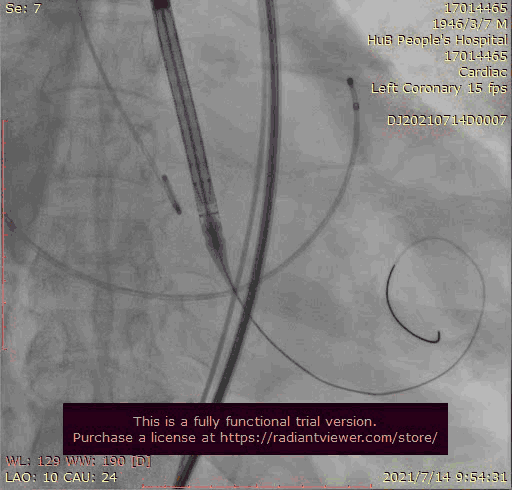

主动脉根部造影

输送器跨瓣